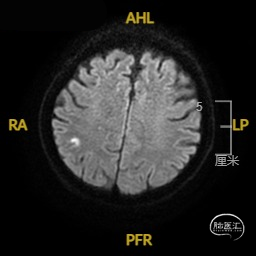

➢ 入院后头核磁检查

患者主因言语不利3天入院,头核磁提示右侧额、顶叶多发低灌注梗塞,脑血管造影提示右侧颈内动脉开口重度狭窄,为责任血管,另外患者前交通动脉、右侧后交通动脉开放不良,并且狭窄严重,考虑到高灌注风险,决定分期处理,一期小球囊扩张改善供血,二期支架成型。